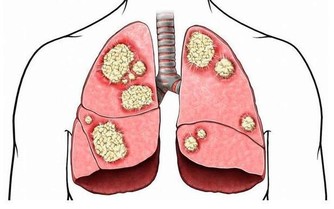

對 症:咳嗽、氣喘、支氣管炎